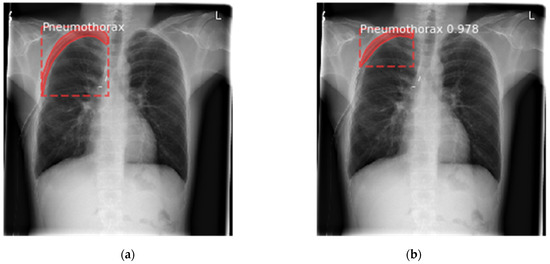

6.1. Results for Segmentation of Pneumothorax